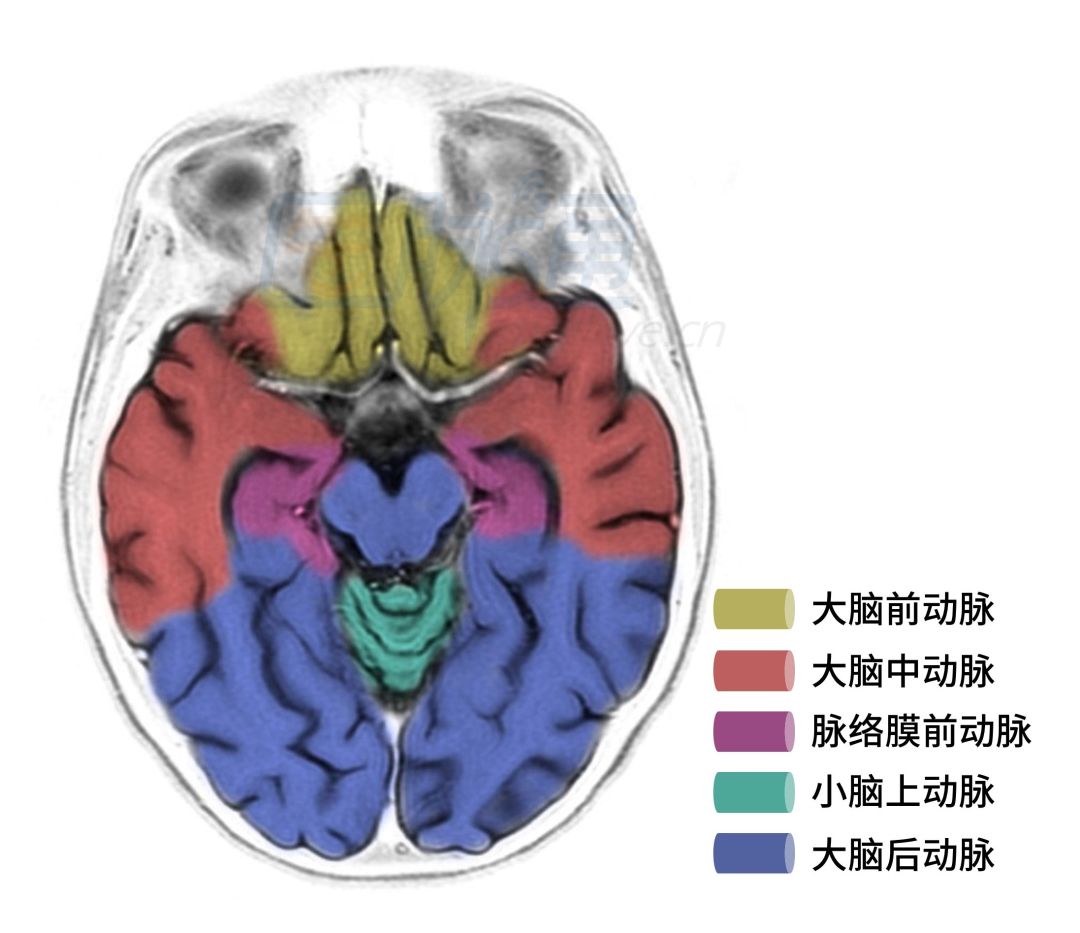

图8 基底节层面

图9 基底节上部层面

图8、9显示的层面主要是额叶、颞叶、枕叶、基底节、胼胝体压部等血管供应区域。

❖ 大脑前动脉:额极动脉供应额上前回的内外侧面,闭塞可引起精神障碍和对侧手部强握反射。胼缘动脉供应额上回的前内侧面及额叶内侧面,闭塞可引起对侧下肢瘫痪及皮层感觉障碍,同时伴有排尿困难。

❖ 内侧豆纹动脉:为大脑前动脉的中央支,其返支(Heubner 动脉)供应纹状体前下部、尾状核头及内囊前下部,闭塞可引起额性共济失调、对侧中枢性的面舌瘫及上肢瘫。

❖ 外侧豆纹动脉:为大脑中动脉的中央支,供应前连合外侧部、壳核、苍白球外侧段、部分额叶眶面皮质、外囊、尾状核头及体部(前下部除外)、内囊前肢和内囊膝部和后肢前部,闭塞可引起对侧上下肢偏瘫而无感觉障碍和偏盲。

❖ 脉络丛前动脉:其中央支供应内囊后肢的后下部和苍白球,闭塞可引起对侧偏瘫、对侧偏身感觉障碍及偏盲。

❖ 大脑后动脉:其深穿支有丘脑膝状体动脉、丘脑穿动脉、脉络膜后内侧、脉络膜后外侧等供应丘脑。丘脑膝状体动脉供应丘脑枕、内外侧膝状体。脉络膜后内侧动脉供应丘脑内侧核后半部分以及内侧膝状体。脉络膜后外侧动脉供应丘脑枕及外侧膝状体。丘脑穿动脉供应丘脑内侧核前半部分、丘脑枕以及外侧膝状体。丘脑膝状体动脉闭塞可致丘脑外侧核受损而引起丘脑综合征。丘脑穿通动脉闭塞可致丘脑外侧核前半部受损而引起红核丘脑综合征。